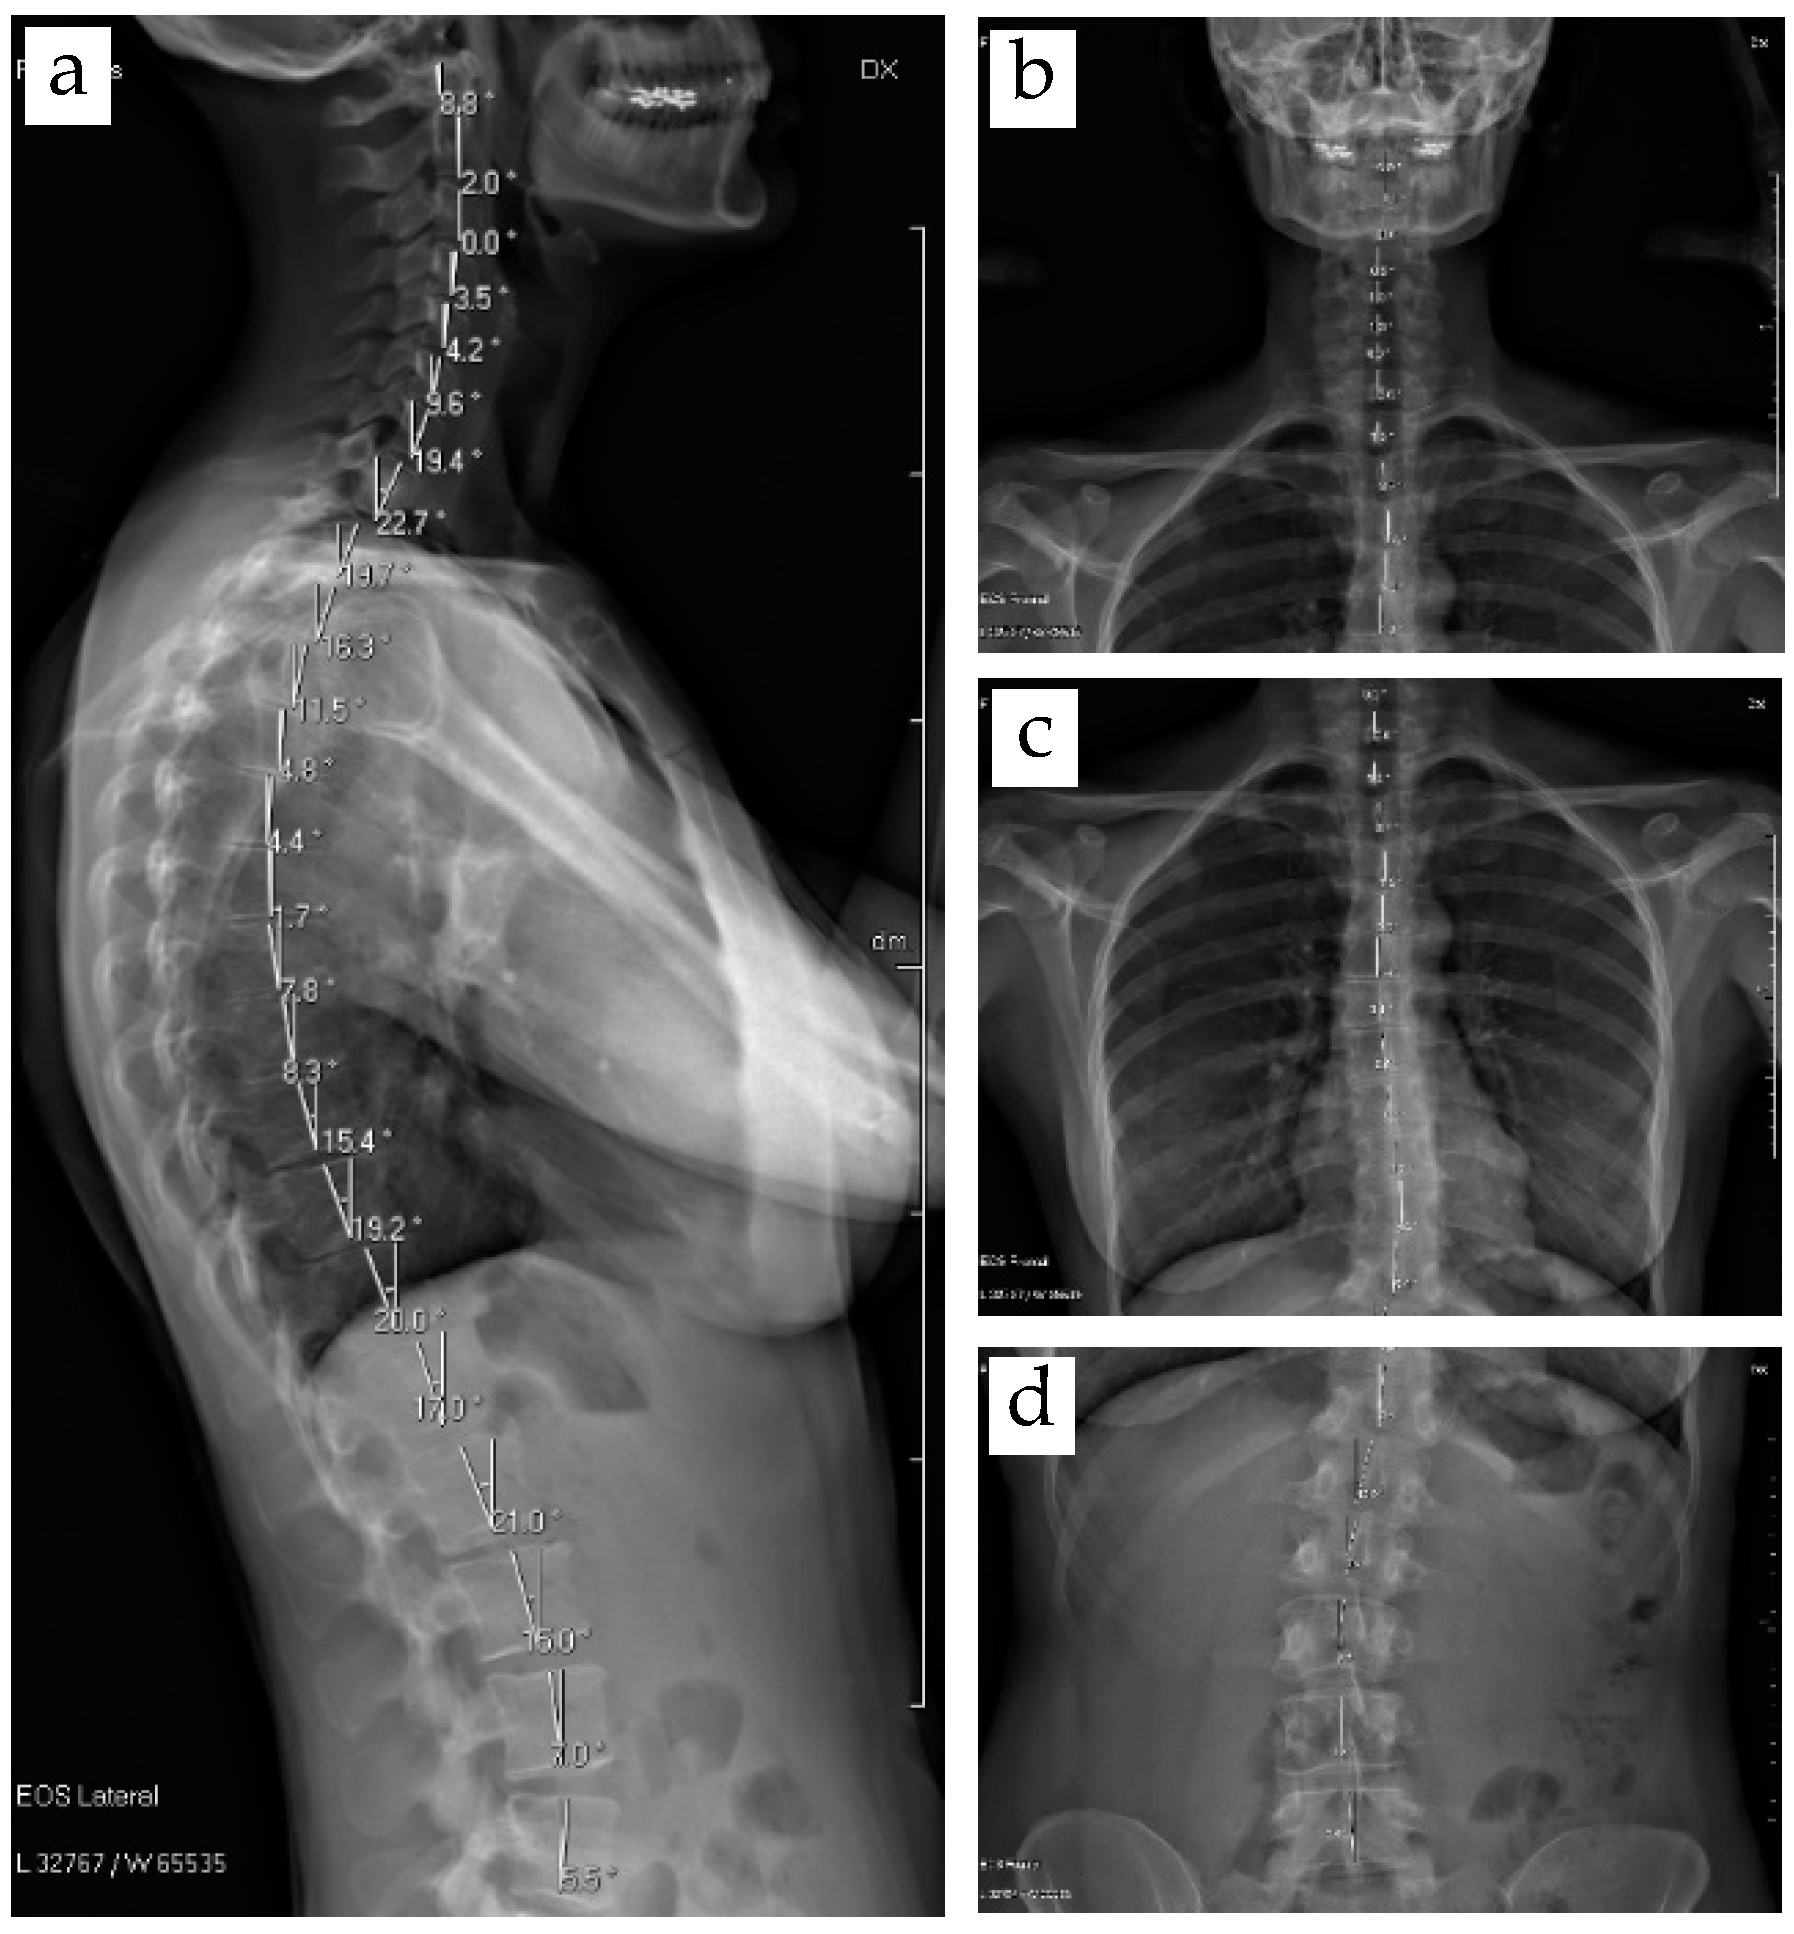

3.3. 3D Modelling of Thorax with Scoliosis-Related Deformities

- Beyer, B.; Sholukha, V.; Dugailly, P.M.; Rooze, M.; Moiseev, F.; Feipel, V.; Van Sint Jan, S. In vivo thorax 3D modelling from costovertebral joint complex kinematics. Clin. Biomech. 2014, 29, 434–438. [Google Scholar] [CrossRef]